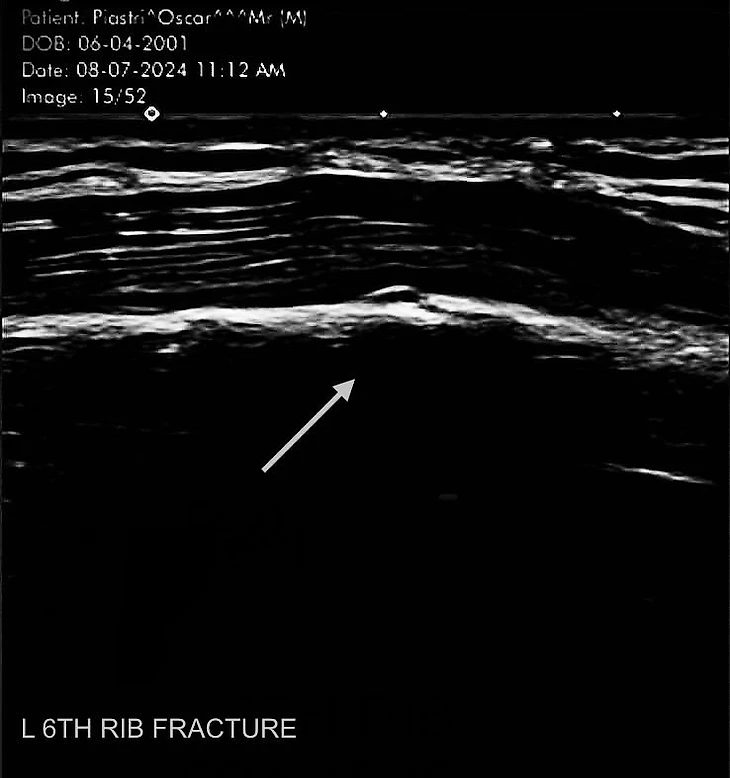

Во время летнего перерыва он подвел итоги первой половины прорывного сезона в социальных сетях, опубликовав четыре фотографии. На одном он стоит с кубком победителя, на двух − празднует попадание на подиум, а на четвертом оказался результат ультразвукового исследования.

«Первая часть сезона завершена. Первая победа на Гран-при. Первая сломанная кость. Ребро наслаждается перерывом».

Таким образом австралиец сообщил, что уже несколько недель восстанавливается от полученной травмы − у него перелом шестого ребра.

Дата на снимке − 8 июля 2024 года − говорит о том, что его сделали в понедельник, сразу после Гран-при Великобритании. Пиастри не сообщает дополнительных подробностей, однако сроки (и подпись) дают понять, что спустя две недели на «Хунгароринге» Оскар победил с крайне неприятным и болезненным повреждением.